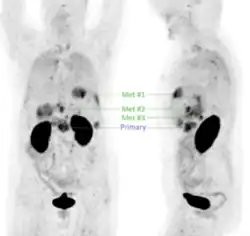

In a cohort of 20 suspected (19 confirmed) head-and-neck squamous cell carcinoma (HNSCC) cases, 68Ga-Trivehexin PET had a higher sensitivity (92.5%), positive predictive value (PPV, 100%), and accuracy (93%) than the standard 18F-FDG PET, for which sensitivity, PPV, and accuracy were 90%, 93.1%, and 84.3%, respectively.[32] 68Ga-Trivehexin was furthermore applied in a case of tonsillar carcinoma metastasized to the brain (see image).[31]